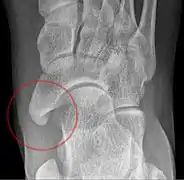

![]() X-ray of the foot showing an accessory navicular bone | |

An accessory navicular bone is an accessory bone of the foot that occasionally develops abnormally in front of the ankle towards the inside of the foot. This bone may be present in approximately 2-21% of the general population and is usually asymptomatic.[1][2][3] When it is symptomatic, surgery may be necessary.